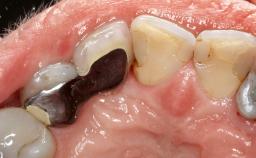

Treatment of Peri-Implantitis at a Zirconia Implant

Frank Schwarz, Ausra Ramanauskaite

Due to their promising clinical performance, zirconia implants have recently become popular alternatives to titanium implants, particularly for areas with high esthetic demands (Holländer and coworkers 2016; Roehling and coworkers 2016; Lorenz and coworkers 2019). However, regardless of the reported high survival and success rates, zirconia implants were affected by peri-implant diseases over the short observation period, suggesting the importance of treating peri-implant diseases at zirconia implants (Becker and coworkers 2017). In their case, Frank Schwarz and Ausra Ramanauskaite present 3-year results following mechanical debridement alongside Er:YAG laser monotherapy.